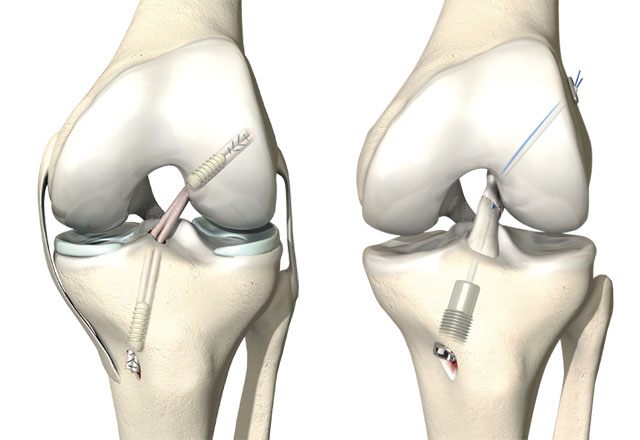

- Cruciate ligament reconstructions (posterior and anterior)